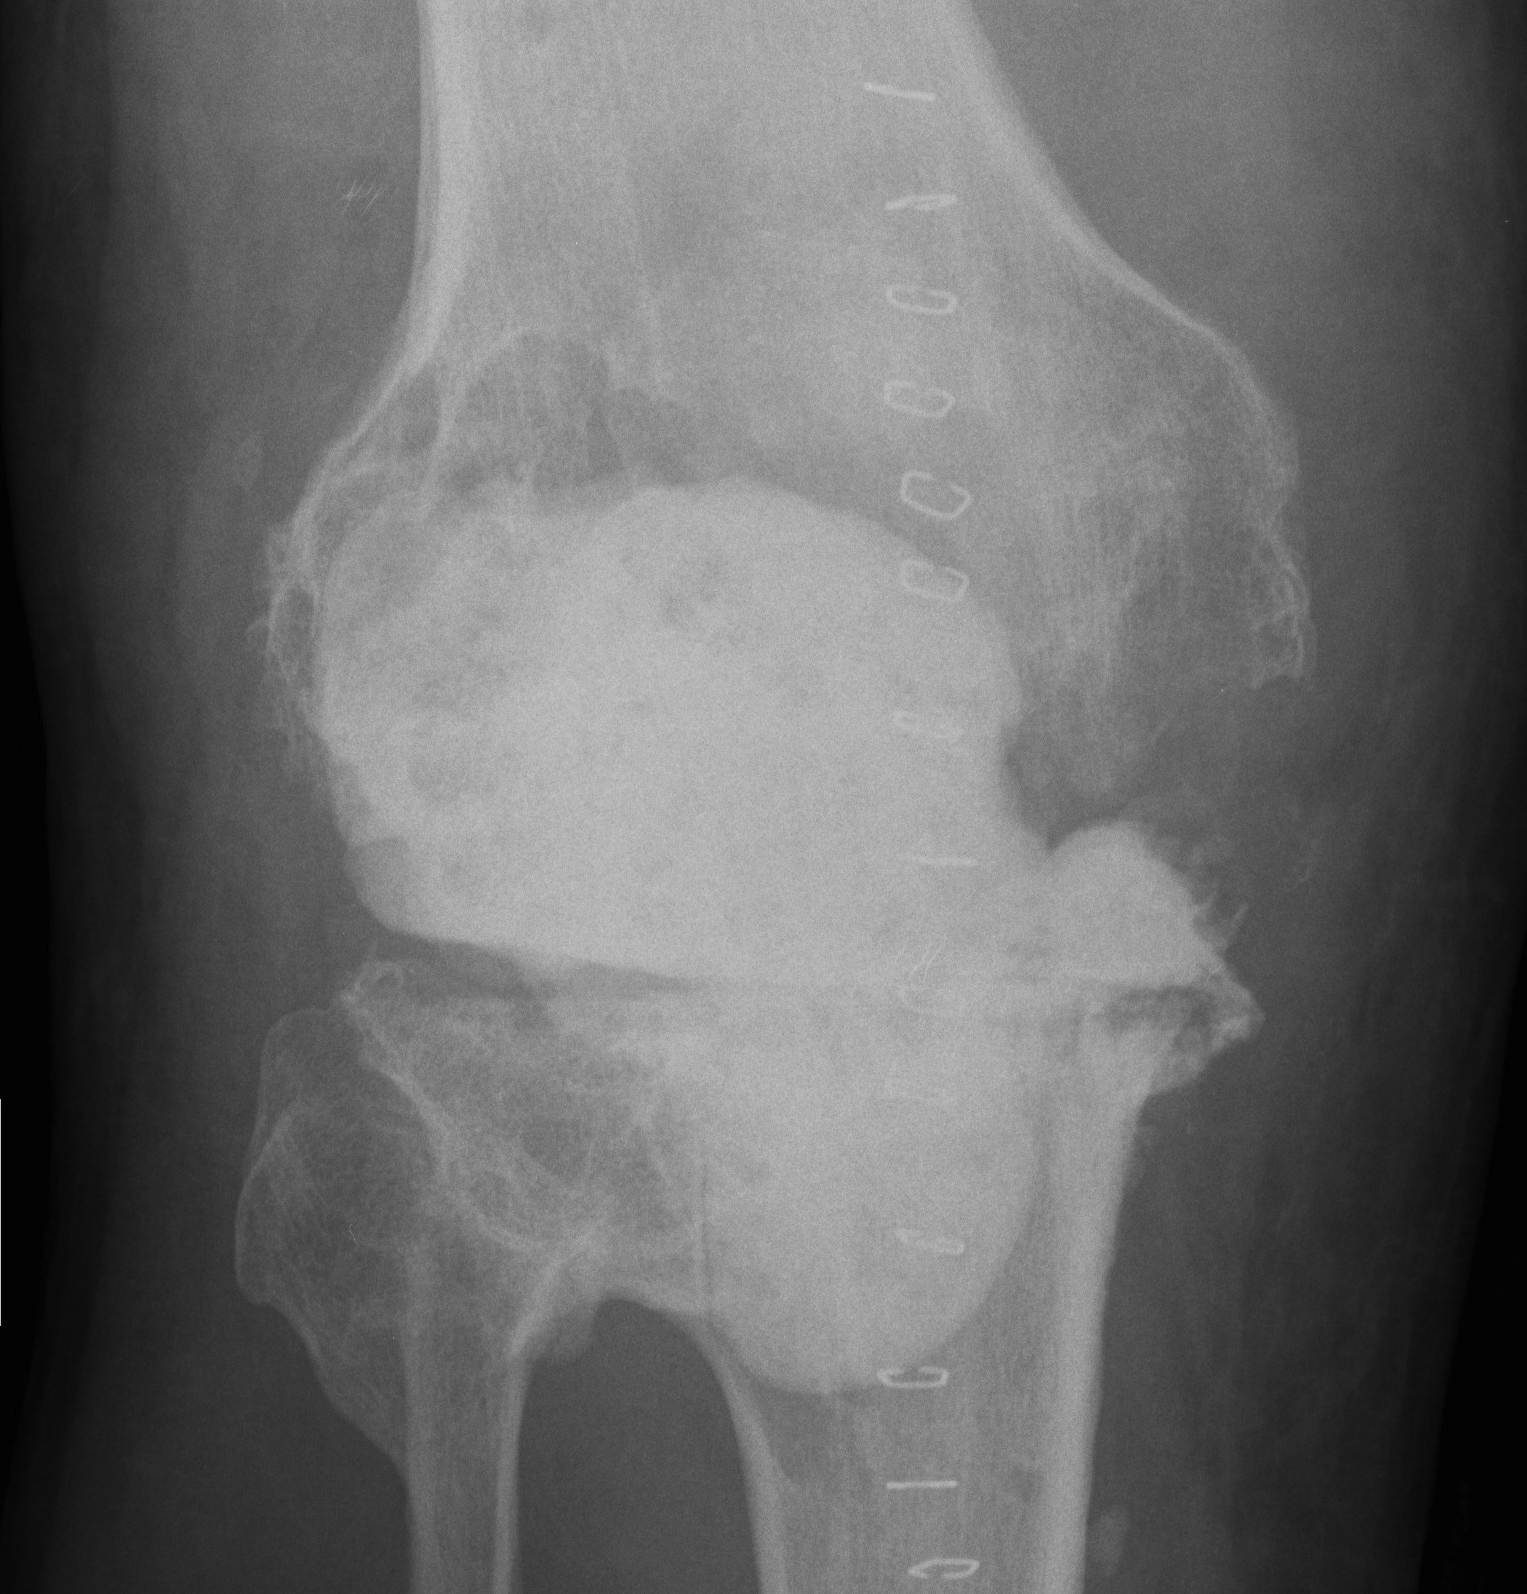

Xray

- progressive early lysis

4. Positive Intra-operative Culture

- presumptive diagnosis aspetic loosening

- intra-operative M/C/S comes back positive (2 out of 5)

2. Two Stage Revision

Indication

- chronic infection

- Loose prosthesis

- failed early washout / debridement